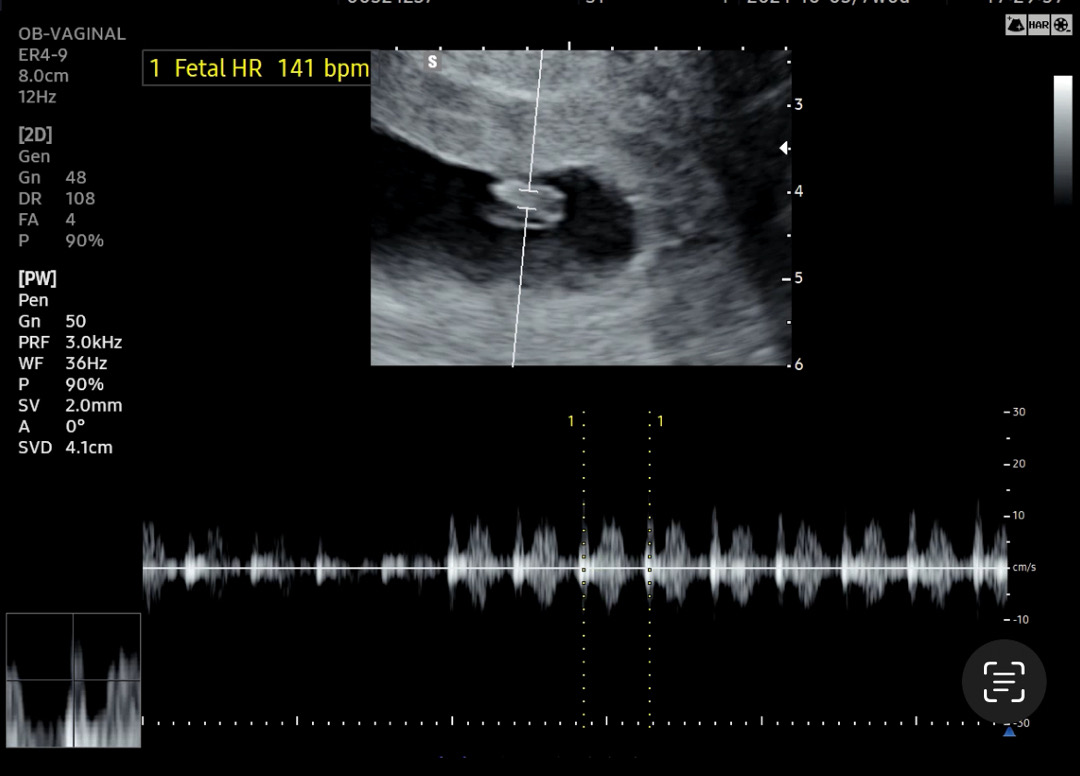

6주4일 심소듣고왔어요!

6주4일차인 어제 심소리 듣고왔어요 못들으면어쩌나했는데 아기집이 너무 커져있어서 놀랐어요 엄청 벌크업했더라구요.. 얼떨떨해요 ㅎㅎㅎ 아기가 생각보다 잘크고있어서ㅎㅎ 신기하네요